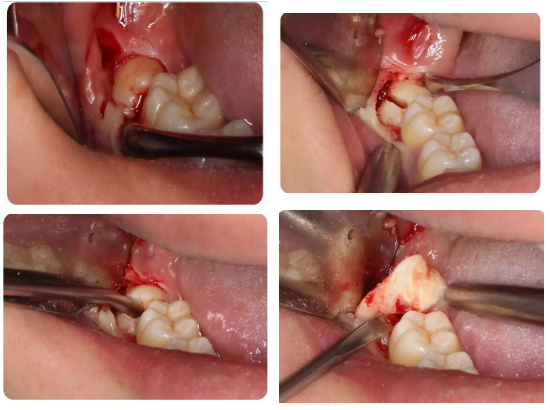

5、下颌第三磨牙的阻力分析及手术设计;

下颌阻生第三磨牙的阻力分析、解除各步骤要点

通过病例讲解各类下颌阻生第三磨牙的微创拔除方法

通过病例分析手术中遇到问题怎样解决